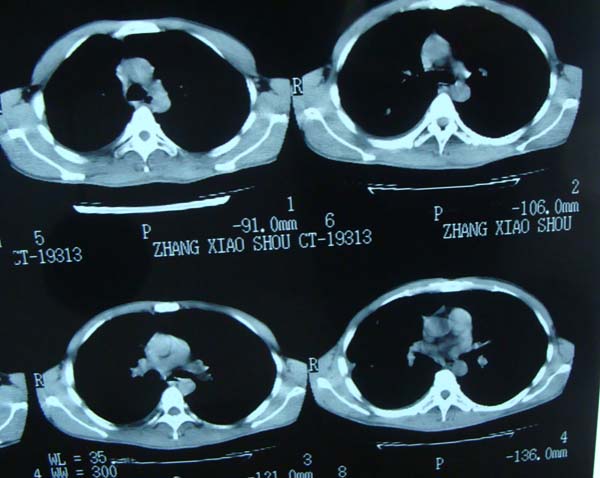

标题: CT15132:男,26岁。建筑混凝土工人。发热。咳。 [打印本页]

标题: CT15132:男,26岁。建筑混凝土工人。发热。咳。

右肺继发型肺结核,右侧胸腔积液、胸膜肥厚粘连。

右肺多发园形结节考虑不考虑转移?

首先考虑结核结节(建议结合实验室检查明确)。转移瘤不能完全除外。

年轻男性,右肺多形性病灶伴右侧胸腔积液,考虑结核

右肺及胸胸膜多个结节多考虑转移瘤,右侧胸水,结核次之。